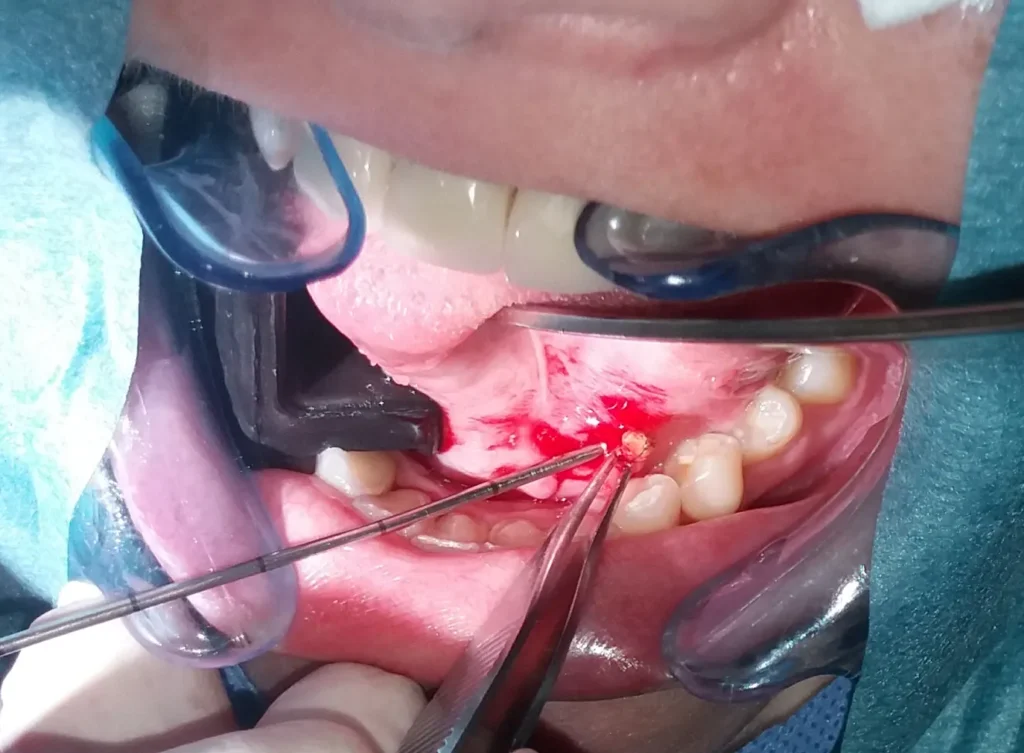

Sijalendoskopija je minimalno invazivno lečenje opstruktivne bolesti pljuvačnih žlezda koje omogućava očuvanje njihove funkcije – minijaturni endoskopi omogućavaju ne samo pregled nego i odstranjivanje kamenaca ili širenje suženih pljuvačnih kanala. Ponekad je zbog veličine ili položaja kamena potrebno pred odstranjivanjem kamena obaviti njegovo razbijanje (litotripsiju) ili operaciji dodati mali rez na sluzokoži usne duplje. Za litotripsiju najčešće koristimo holmijumski laserski snop. Sialendoskopija se pokazala korisnom u terapeutskom smislu i kod juvenilnog relapsnog parotitisa, a i kod parotitisa koji je posledica lečenja radioaktivnim jodom.